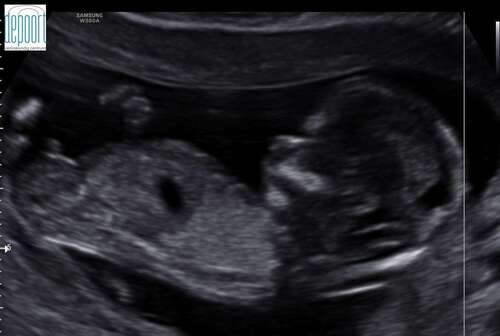

Hierbij nog een foto.. Weet alleen niet of je hier iets kan uithalen. Foto is van 14+2

Nog een tweede foto. Ik ben hier 13w en 5dagen